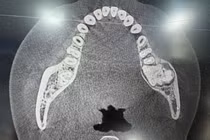

Hình ảnh khối u trước và sau mổ - Ảnh BVCC

Kết quả chụp CT cho thấy ổ dịch áp xe tuyến nước bọt hai bên mang tai, kích thước bên phải 5x3cm, bên trái 3x2cm; khối chắc, di động tốt, mô mềm xung quanh phù nề, có vài hạch phản ứng. May mắn là khối u chưa gây viêm nhiễm hay chèn ép vùng lân cận, cũng không ảnh hưởng đến chức năng vận động của hàm.